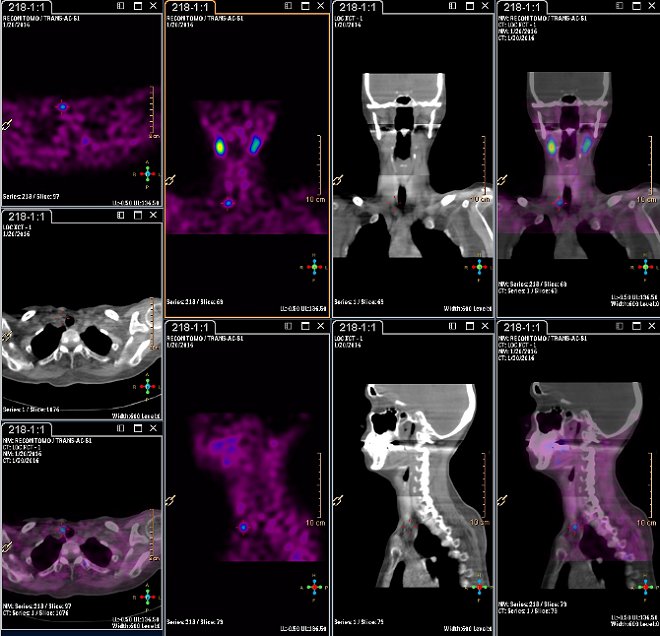

/ Obr.3: Scintigrafie pomocí 99mTc-MIBI metodou SPECT/ldCT (General MPR fusion) se zřetelnou patologickou ložiskovou depozicí radiofarmaka

lokalizovanou ventrokaudálně od dolního pólu pravého laloku štítnice. /

/ Obr.4:

Scintigrafie pomocí 99mTc-MIBI metodou SPECT/ldCT se zřetelnou patologickou ložiskovou depozicí radiofarmaka

lokalizovanou ventrokaudálně od dolního pólu pravého laloku štítnice.